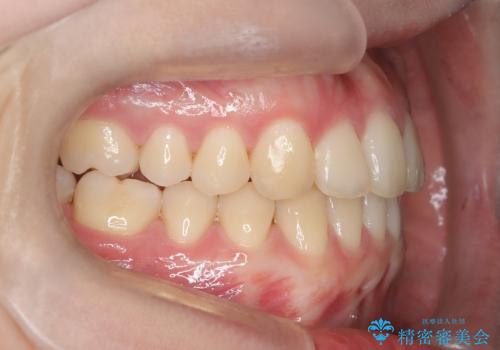

インビザラインとワイヤー矯正の併用で綺麗な歯並びに!

- 前歯のガタツキが気になるとのことで来院されました。

ワイヤー矯正とインビザライン矯正を併用することによって、治療期間の短縮と、より良い仕上がりを目指す治療を選択することとしました。

インビザライン(アライナー)矯正とワイヤー矯正のそれぞれの利点を生かした治療を行い、綺麗な歯並びになりました。